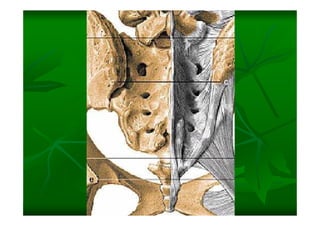

Este documento describe la columna vertebral humana. Está compuesta de 33 vértebras divididas en 7 cervicales, 12 torácicas, 5 lumbares, 5 sacras y 4 cóccigeas. Cada vértebra posee un cuerpo, pedículo, apófisis transversas, apófisis espinosa e inferior y laminas. Las curvaturas de la columna son la lordosis cervical y lumbar y la cifosis torácica y sacra.